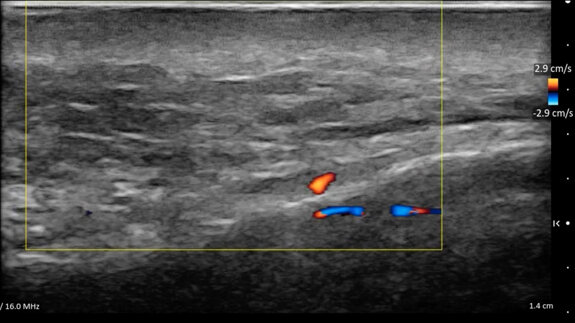

• Mappatura vascolare dinamica: l’integrazione di B Mode, Color Doppler e del Power Doppler rappresentano la frontiera della sicurezza. Vasi critici posti in posizioni anatomiche critiche come l’arteria angolare possono avere decorsi variabili. L’esame ecografico permette di mappare questi vasi prima di inserire l’ago, scegliendo il piano di correzione (superficiale o profondo) che garantisca l’assenza totale di rischio vascolare occlusivo intravascolare o compressivo extravascolare (Fig. 9).

Fig. 9 - L’arteria angolare in Color Doppler.